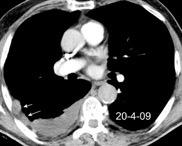

Chohan K et al. A review of respiratory manifestations and their management in Ehlers-Danlos syndromes and hypermobility spectrum disorders. Chronic Respiratory Disease. 2021 Hemotórax frecuente por rotura arterial. Enfermedad del tejido conectivo con hipermovilidad articular, textura de piel anormal y fragilidad del tejido conectivo. (Especialmente en el subtipo vascular)

Ehler Danlos vascular tipo IV. Hemoptisis con hemotórax y hematoma mediastínico. Embolización. 4º día: Fallece por rotura de la arteria esplénica.